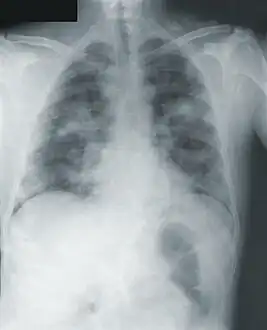

Image -primary pneumonic plague obtained on illness days 2, 3, and 18 shows bilateral lower lung zone predominant airspace disease associated with bilateral pleural effusions

Image -primary pneumonic plague obtained on illness days 2, 3, and 18 shows bilateral lower lung zone predominant airspace disease associated with bilateral pleural effusions Chest x-ray of pneumonic plague showing bilateral, diffuse interstitial pleural infiltrates, and accompanying consolidation. As well as, what appeared to be marked, mediastinal adenopathy.

Chest x-ray of pneumonic plague showing bilateral, diffuse interstitial pleural infiltrates, and accompanying consolidation. As well as, what appeared to be marked, mediastinal adenopathy.